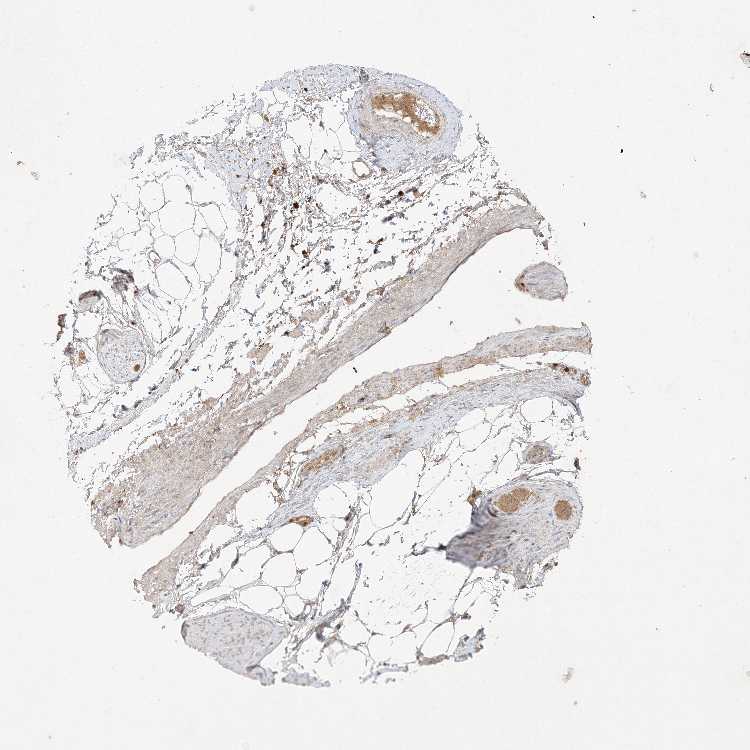

SOFT TISSUE 1 - Antibody stainingi

Antibody staining in the annotated cell types in the current human tissue is reported as not detected, low, medium, or high, based on conventional immunohistochemistry profiling in selected tissues. This score is based on the combination of the staining intensity and fraction of stained cells.

Each image is clickable and will lead to virtual microscopy that enables deeper exploration of all samples and also displays staining intensity scores, fraction scores and subcellular localization as well as patient and tissue information for each sample.

Antibody HPA054975Antibody CAB011464Antibody CAB035990Antibody CAB080407

Chondrocytes LowMediumNot detected-

Fibroblasts Not detectedLowLowNot detected

Peripheral nerve -LowLowNot detected

SOFT TISSUE 2 - Antibody stainingi

Chondrocytes --LowNot detected

Peripheral nerve LowMedium-Not detected